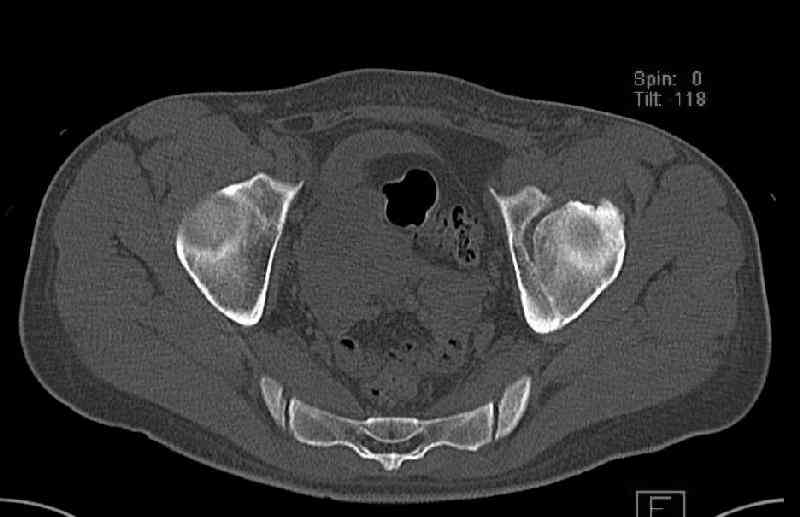

Нелеченный перелом вертлужной впадины

Мужчина 33 лет получил травму в шахте (придавило вагонеткой) 6 недель назад. Изолированное повреждение вертлужной впадины.

В местной больнице отлежал несколько недель на вытяжении. После выписки амбулатрный травматолог направил в институт. На сегодня, похоже, уже имеется неправиильное сращение. См. картинки.

Вопрос - что делать сейчас? Оставить как есть или идти на открытое восстановление? Если последнее, то какой доступ, репозиционные манипуляции и фиксацию тут можно посоветовать? Заранее спасибо.

Dear all, A male 23 y.o. injured 6 weeks ago - mine trauma, impacted by a carriage. Isolated injury of the acetabulum. At the initial hosptial was on bed traction some weeks. After discharge visited anotheк orthopaedic surgeon who referred him to our unit. To date looks like a malunion. Images attached. The question is about what to do now - either leave it as is or perform open reduction? If the latter what approach, reduction manoeuvres and fixation would you advice? Thx in advance!